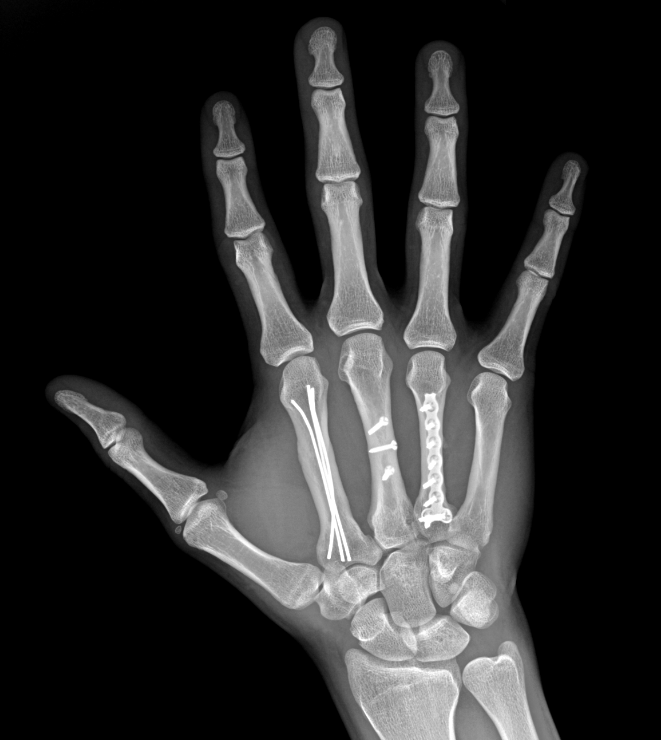

• Перелом ключицы

Перелом ключицы

2022-10-21

Переломы ключицы являются одними из самых частых переломов, на их долю приходится 3% всех переломов.Исторически его лечили консервативно, но результаты не всегда были положительными.Неоперативное лечение может привести к таким осложнениям, как боль, неправильное сращение и синдром грудной апертуры.Благодаря усовершенствованию методов хирургической фиксации многие хирурги решили использовать хирургическую фиксацию для лечения переломов ключицы со смещением.